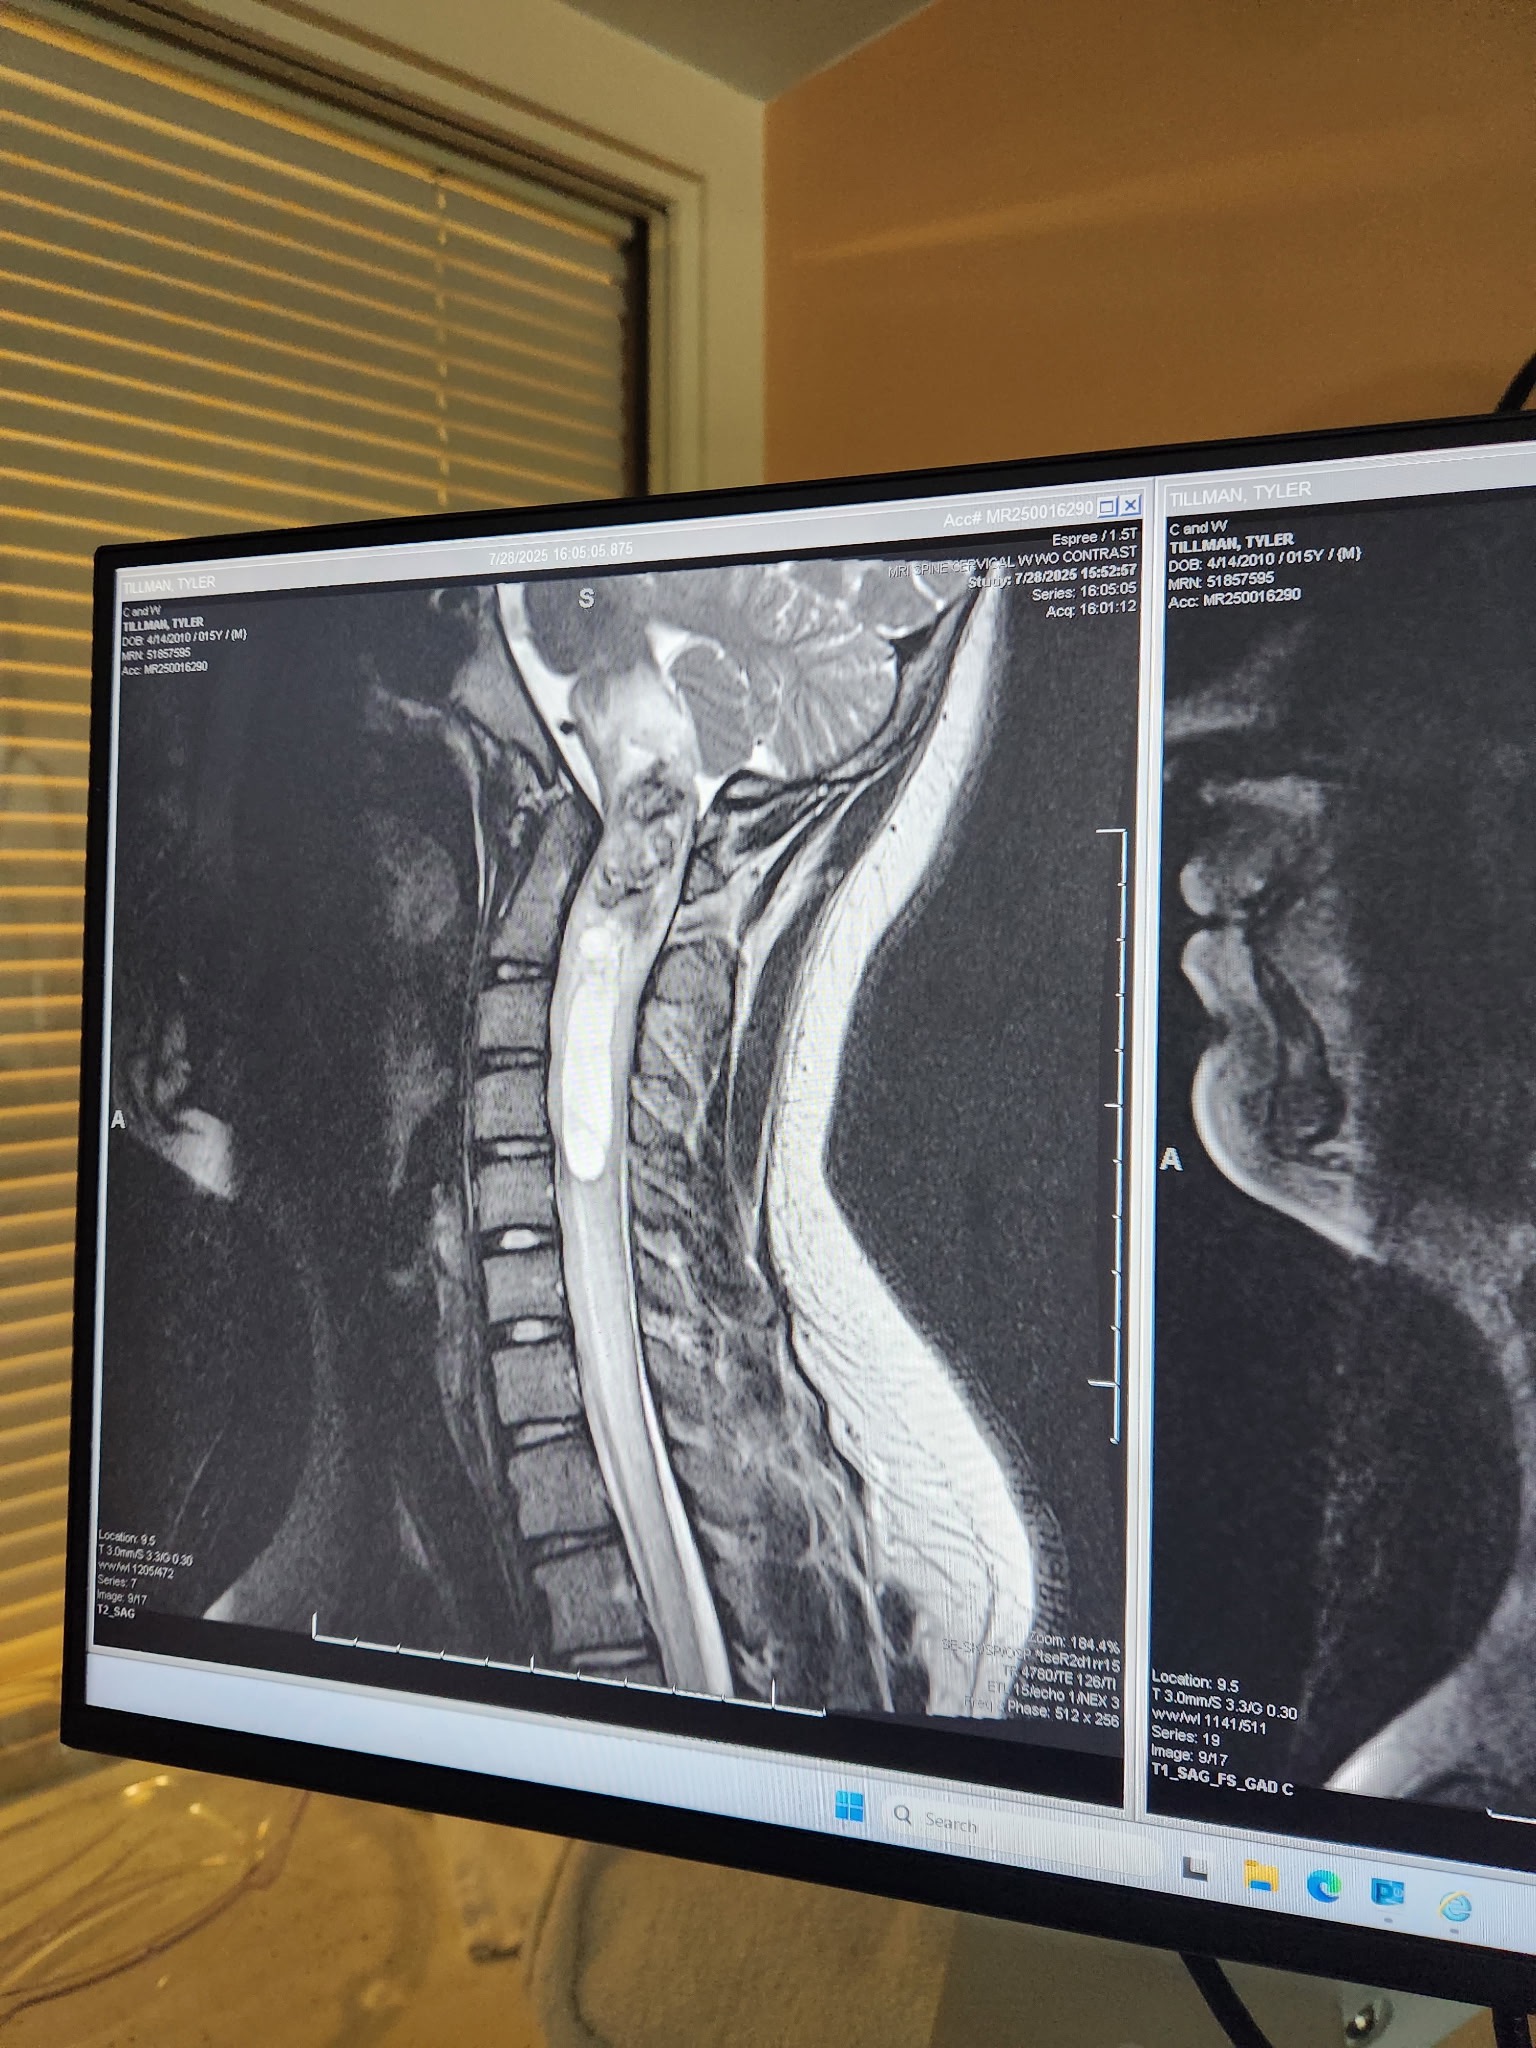

Tyler was recently diagnosed with a tumor on his brain stem — one of the most delicate and critical areas of the brain. He is scheduled to undergo major brain surgery this coming Monday.